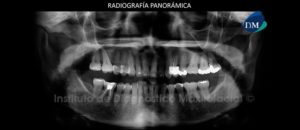

Paciente masculino de 17 años de edad acude al Instituto de Diagnóstico Maxilofacial debido a que clínicamente no se visualiza la pieza 35. Para lo